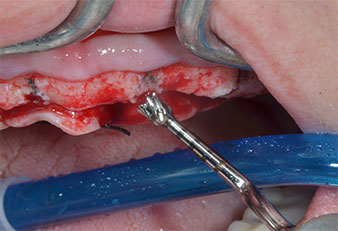

Пиезоелектрически инструмент с диамантено покритие с форма на пламък (Piezomed I1) e използван за маркиране на позициите на имплантите и за пилотна подготовка (Фиг. 3). Препарацията беше извършена с внимателни вертикални движения, с намалена мощност, пълна иригация и лек натиск (под 300 g) След това се приложи пилотен инструмент (Piezomed I2A/ I2P) за първоначално увеличение на диаметъра на имплантното ложе с 2 mm (Фиг. 4), последвано от 3 mm разширение (Фиг. 5)

В настоящия случай инструменти Z25P и Z35P не са използвани поради сравнително меката задна кост, която лесно се обработва с I3A/I3P.

Поради сравнително твърдата кост (D2) в тази област, 10-милиметровото имплантно ложе в позиции 11 и 21 беше завършено с ротационен дрил с диаметър 4 mm в комбинация с W&H хирургичен обратен наконечник WS-75 L, W&H имплантологичен мотор Implantmed и опционалния W&H Osstell ISQ модул. За разлика от това, благодарение на меката кост, дисталните зони се подготвят до окончателен диаметър 3 mm, използвайки накрайник за Piezomed I3P. Имплантите най-накрая са поставени трансгингивално, за да остеоинтегрират за три месеца (Фиг. 6-10). Съществуващата протеза се фиксира на четирите временни импланта (Фиг. 8).